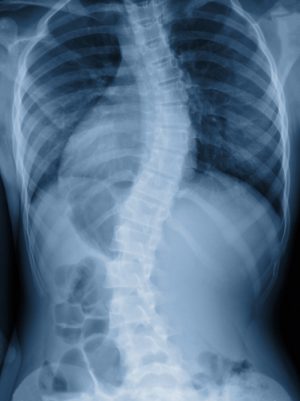

Сколиоз – это боковое искривление позвоночника, которое происходит в трех плоскостях. Зачастую данная патология начинается в раннем детском возрасте и прогрессирует в юношестве. В настоящее время существует несколько классификаций сколиоза в зависимости от заданного параметра.

По форме деформации позвоночника выделяют:

- Сколиоз с С-образным искривлением (отмечается одна дуга искривления).

- Сколиоз с S-образным искривлением (наблюдаются две дуги искривления).

- Сколиоз с Z-образным искривлением (отмечается три дуги искривления).

В зависимости от угла наклона позвоночника различают четыре степени прогрессирования заболевания:

- Первая – угол наклона меньше 10 градусов.

- Вторая – угол искривления составляет 11-25 градусов.

- Третья – угол наклона 26-50 градусов.

- Четвертая – угол искривления составляет более 50 градусов.

Консультация лечащего врача-ортопеда или спинального хирурга. Врач осматривает пациента, знакомится с историей болезни и назначает серию инструментальных исследований, которые позволят поставить точный диагноз.- Рентгенологические исследования. Изучаются рентгенографические снимки позвоночника в двух проекциях, благодаря которым можно определить место и степень искривления.